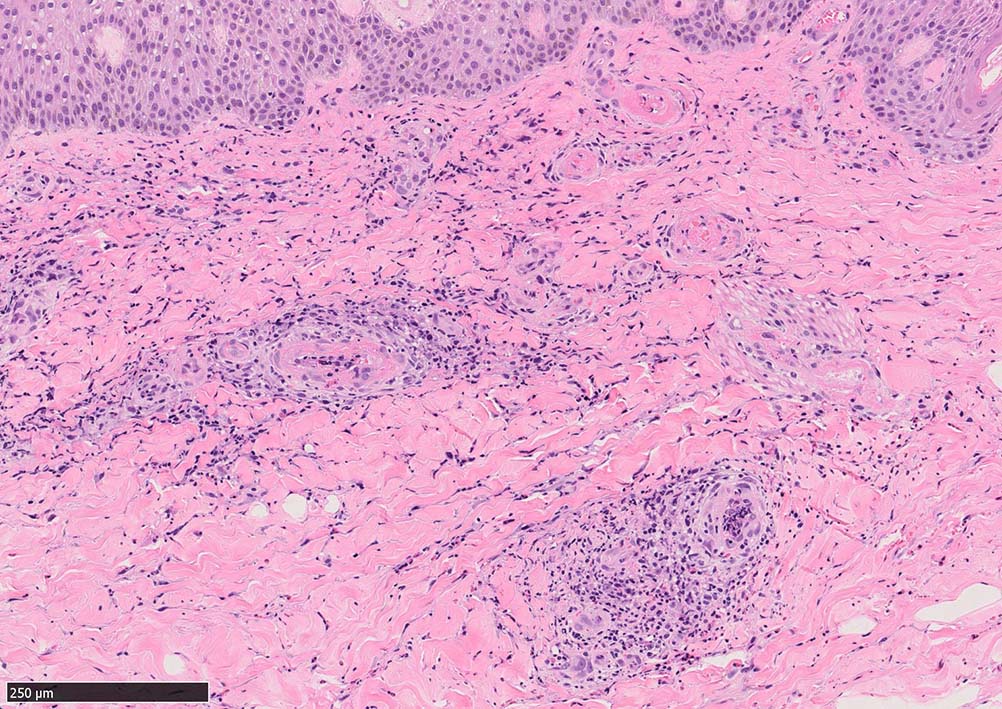

痂皮の下に硝子様凝固物があり, 周囲には壊死組織が形成されている. 近傍の細血管には凝固物による閉塞の所見があるように見える. 連続する細血管には, fibrinoid necrosisを呈する壊死性血管炎が認められる.

マダニ科マダニ(4属)では触肢と口器は短くなっており,そのために, 吸血後24時間程度経過すると,唾液腺で産生されるセメント様物質を分泌して口下片全体を包みこみ,体を宿主にしっかりと固定する.

(case02の皮膚表面にみられる硝子様の層がそれに相当するようです。)

セメント様物質を注入した後には抗凝固物質(抗トロンボキナーゼ活性因子,アピラーゼによる抗血小板活性など)を分泌して,血液の凝固を防ぐ。加えて,エステラーゼ,アミノペプチダーゼ,プロスタグランジンE2などの物質を含む唾液を分泌して局所の炎症,充血,浮腫,出血などを引き起こし,吸血をより容易にしている。さらに飽血が近ずくとセメントを溶解する成分を含んだ唾液を分泌して,虫体は宿主から離脱することができるようになる。